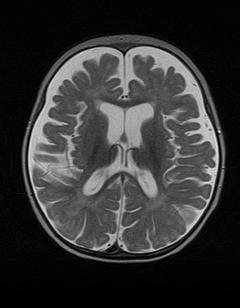

Completammo gli accertamenti della bimba con una RMN encefalica, risultata nettamente patologica (Figura 1).

Figura 1. RMN alla diagnosi: ampliamento degli spazi liquorali periencefalici fronto-temporali e delle cavit� ventricolari di significato atrofico, lieve atrofia del verme cerebellare, corpo calloso modicamente assottigliato, ipofisi di dimensioni ridotte e mielinizzazione ritardata in rapporto all� et� e corrispondente a circa 6 mesi.